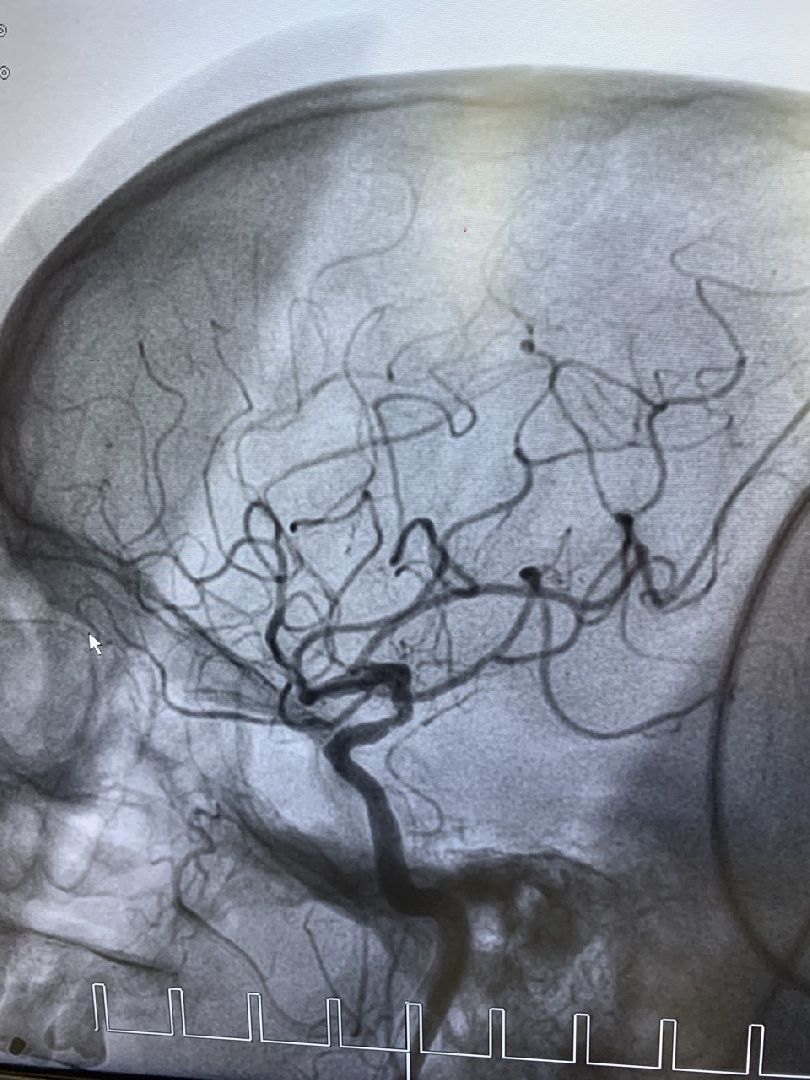

В Региональном сосудистом центре, который является частью Дмитровской областной больницы, освоили лечение ишемического инсульта методом эндоваскулярной ромбоэкстракции. Этим методом хирурги восстанавливают кровоток в пораженной артерии мозга.

Наряду с тромболизисом — растворением тромбов специальным препаратом — в региональном сосудистом центре теперь проводят процедуру тромбоэкстракции. Это высокотехнологичный метод извлечения тромбов из пораженных участков при помощи специальных инструментов.

Фото предоставлены Региональным сосудистым центром